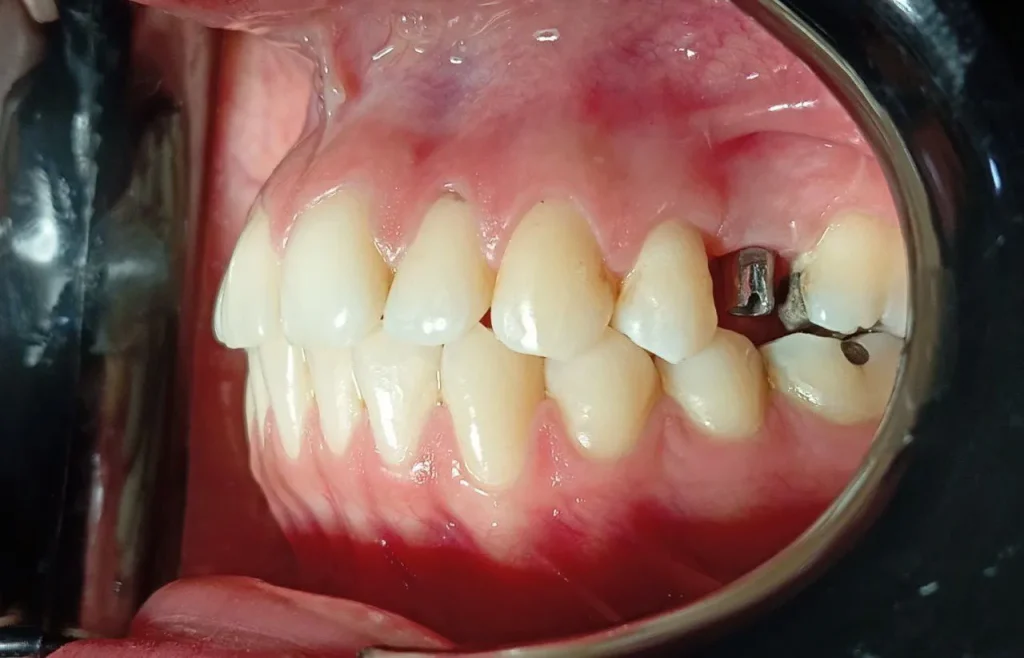

ایمپلنت مطمئن ترین و محبوب ترین روش برای کاشت دندان و جایگزینی دندان های از دست رفته می باشد. ایمپلنت دندان یک پایه از جنس تیتانیوم است (فیکسچر) که به عنوان ریشه دندان درون استخوان فک قرار میگیرد و روکش ایمپلنت دندان بر روی آن قرار میگیرد.

خنده زیبا و وجود تمام دندان ها باعث تقویت حس اعتماد به نفس میشود . ایمپلنت راهی نوین در دندانپزشکی برای جایگزین سازی دندان های از دست رفته میباشد که از خدمات اختصاصی کلینیک مهر شریعتی نیز محسوب می شود. گاهی به هر دلیلی فرد مجبور است دندان های خود را بکشد یا دندان های او ممکن است بر اثر ضربه یا پوسیدگی یا بیماری های لثه از دست رفته باشند که در این شرایط بهترین جایگزین ایمپلنت میباشد دندان ها علاوه بر نقشی که در جویدن غذا دارند امروزه نقش پر رنگ تری در ظاهر زیبا و به اصطلاح خنده زیبا دارند. برای انجام مشاوره با کلینیک مهر شریعتی همراه باشید

ایمپلنت دندان (Dental implants) یکی از پیشرفتهترین و موثرترین روشها برای جایگزینی دندانهای از دست رفته است که مراحل آن نیازمند دقت و مهارت بالای متخصصان دندانپزشکی است. این فرآیند شامل چندین مرحله مختلف است که هر یک به نحوی به بهبود و موفقیت نهایی ایمپلنت کمک میکنند.

در مرحله دوم ، کاشت پایه یا فیکسچر انجام میشود. این مرحله یکی از مراحل کلیدی است در این مرحله پایه فلزی درون استخوان فک کاشته میشود و با گذشت زمان، استخوان به اطراف پایه رشد کرده و آن را محکم میکند.

پس از کاشت پایه، هیلینگ کپ یا تاج موقت روی آن قرار میگیرد تا لثه به درستی شکل بگیرد و از ایمپلنت دور شود. پس از اینکه لثه بهبود یافت و ایمپلنت به استخوان فک جوش خورد، اباتمنت روی پایه قرار میگیرد و تاج موقت دندان به مدت ۴ تا ۶ هفته روی آن گذاشته میشود تا تاج دائمی ساخته و طراحی شود. در نهایت، قالبگیری و ساخت روکش دائمی انجام میشود و تاج دائمی با استفاده از چسبهای قوی روی اباتمنت قرار میگیرد تا ظاهر زیبای دندان حفظ شود.